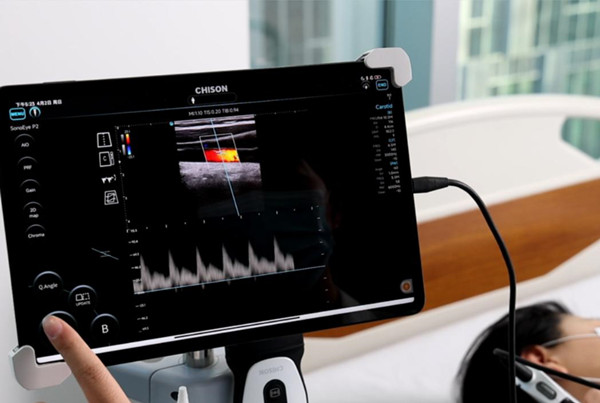

Real-Time Visualization

Healthcare providers can use handheld ultrasound devices to show patients real-time images of their internal organs and structures. This visual aid helps patients understand their conditions better and appreciate the diagnostic process. Improved understanding often leads to increased trust and confidence in the care they receive.